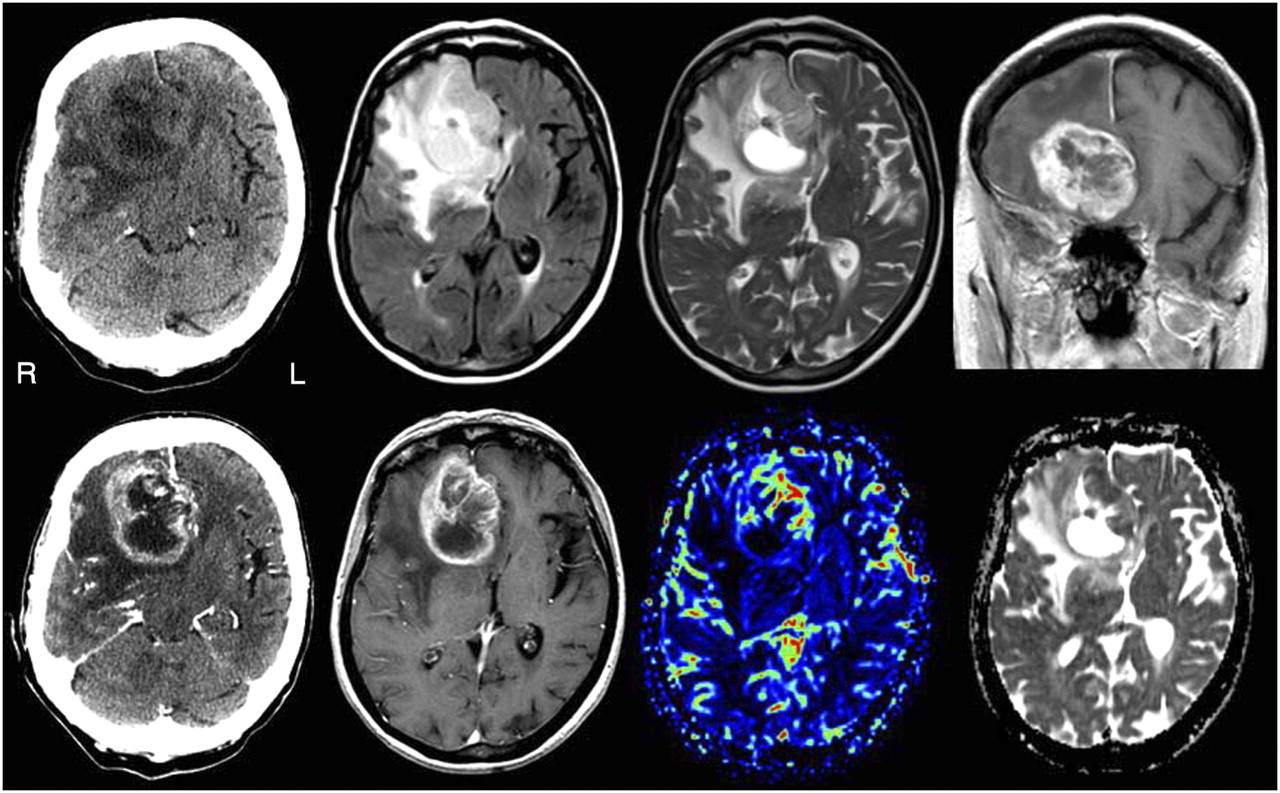

Brain Tumors - Malignant

A cancerous or non-cancerous mass or growth of abnormal cells in the brain, Brain tumors can be treated via Radiation therapy or Radiosurgery.

Radiation therapy uses proton energy beams to kill tumor cells. Usually an external beam radiation is used for this procedure which focuses just on the area of your brain where the tumor is located.

Symptoms include new or increasingly strong headaches, blurred vision, loss of balance, confusion and seizures. In some cases, there may be no symptoms